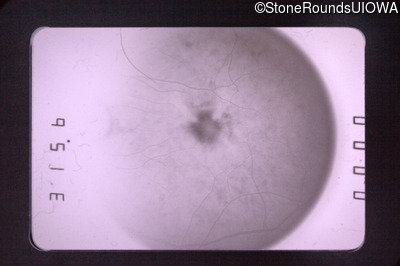

Visit at age: 47 years

Fundus Photography - Right - 20/70